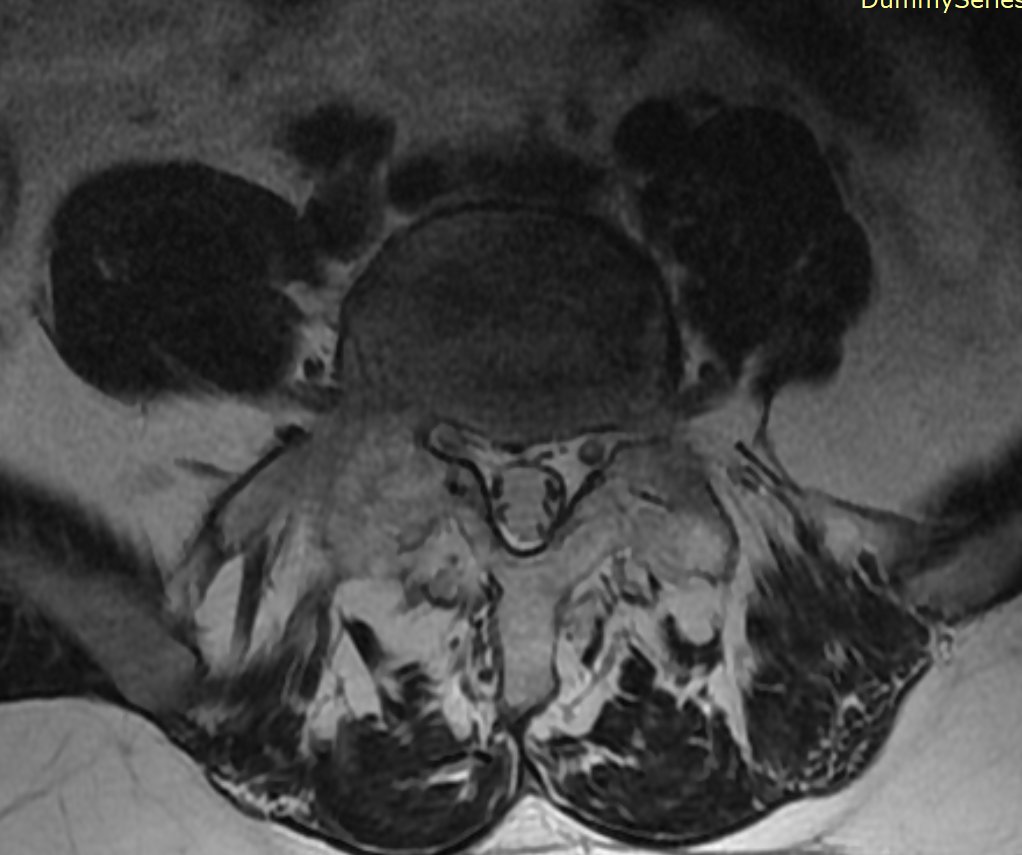

70y/o👩🏾‍🦳.Expansile lession w/mild mass effect on the conus medullaris&cauda equina. Scalloping of the posterior elements. HighT2 signal No DWI anomaly. Most likely spinal(apparently)extradural arachnoid cyst. Same date brain MR:no brain sag nor congestion #spinerad @The_ASSR

josealejandrobv's tweet image. 70y/o👩🏾‍🦳.Expansile lession w/mild mass effect on the conus medullaris&cauda equina. Scalloping of the posterior elements. HighT2 signal No DWI anomaly. Most likely spinal(apparently)extradural arachnoid cyst. Same date brain MR:no brain sag nor congestion #spinerad @The_ASSR